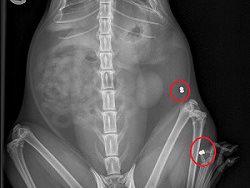

Upon examination, the vet was able palpate his abdomen and felt a suspected slug gun pellet. He was placed on oxygen to stabilise him as he was in a critical stage. Once improved, Richie could have investigative x-rays.

Three slug gun pellets were found; one on the right fore, one on the left hind leg and one in the chest causing bleeding in the lungs and subcutaneous emphysema. (air escaping from the lungs, leaking under the skin)